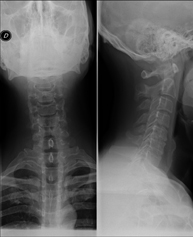

- RX Columna cervical

Técnica mediante la cual, utilizando rayos X, se obtienen imágenes de la columna cervical para su estudio. Indicaciones: traumatismo, dolor cervical. - RX Columna dorsal

Técnica mediante la cual, utilizando rayos X, se obtienen imágenes de la columna dorsal para su estudio. Indicaciones: traumatismo, dolor de espalda. - RX Columna lumbar

Técnica mediante la cual, utilizando rayos X, se obtienen imágenes de la columna lumbar para su estudio. Indicaciones: ciática, traumatismo, dolor lumbar. - RX Sacro-cóccix

Técnica mediante la cual, utilizando rayos X, se obtienen imágenes del sacro y del cóccix para su estudio. Indicaciones: traumatismo, dolor sacro o coccígeo. - Telerradiología columna

Técnica mediante la cual, utilizando rayos X, se obtienen imágenes de toda la columna vertebral para su estudio, valorando especialmente la presencia de escoliosis y dismetrías pélvicas.